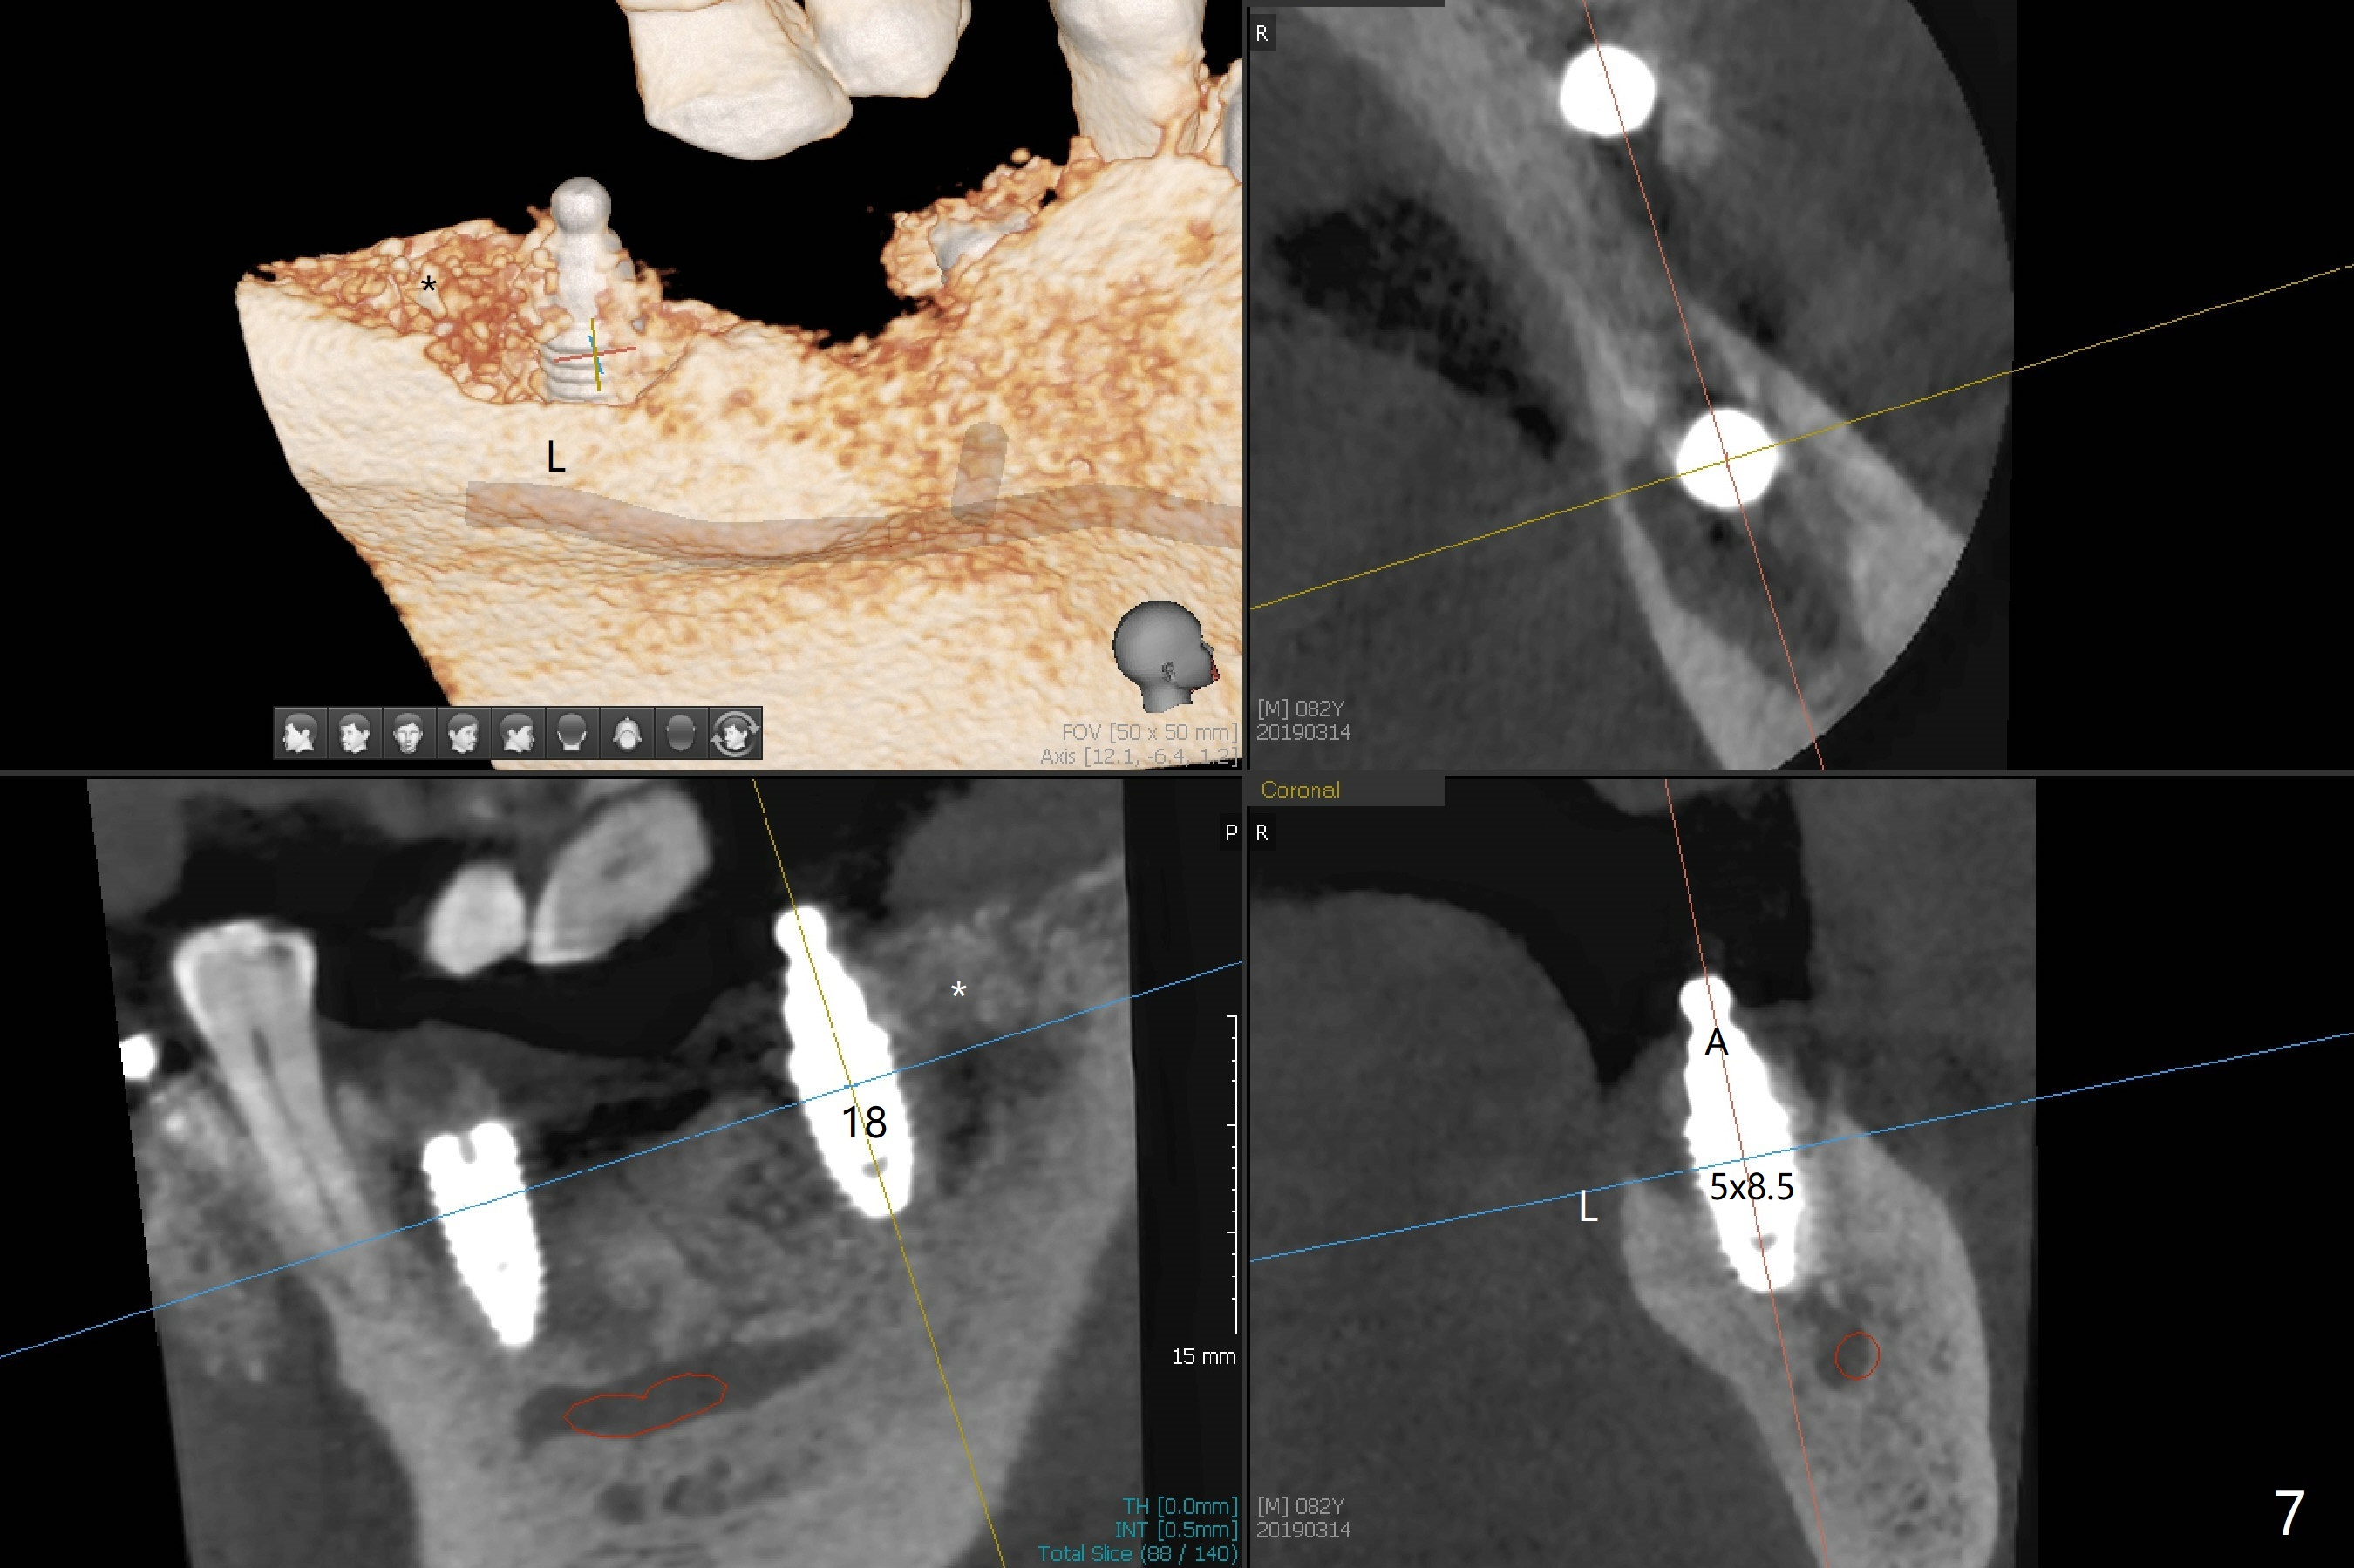

Three months post socket preservation (with buccal plate loss previously), a 3.5x11.5 mm implant is placed at #27 subcrestal (Fig.1). When implants are placed at #22 and 20 (Fig.2,4), threads are exposed buccal (B). Mixture of autogenous bone and allograft is placed to cover the exposed threads (Fig.3,5) following deep placement at #20. For safety, the implant at #20 is buried. Pain control at #18 is poor when initial osteotomy is being established (Fig.6 *), as related to severe infection. Repeated block anesthesia allows to finish implant placement with primary stability; a 3.5x2 mm ball abutment is placed (Fig.7). With placement of 2 other ball abutments at #27 and 22 (Fig.3), the lower existing RPD is converted to a removable provisional (Fig.8). With addition of acrylic, the socket of #20 is covered (Fig.9). There is no apparent bone #20 distal 3 months postop (Fig.10,11 <). Re-graft is needed? The implant at #21 appears immediately subgingival 5 months postop (Fig.12 *). The distobuccal threads are exposed (Fig.13). After decortication, allograft is placed, followed by 6-month membrane. In fact, a shorter and smaller implant should be placed instead. The patient has to wear the RPD for mastication. It would be more painful without it. Later the tissue surface of the RPD is trimmed.